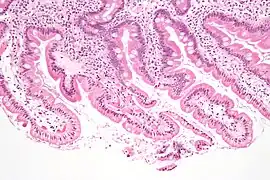

Sección de duodeno de gato

Duodeno con depósito de amiloide en lámina propia

Ribete de cepillo y microvellosidades duodenales

Micrografía mostrando giardiasis en biopsia duodenal.